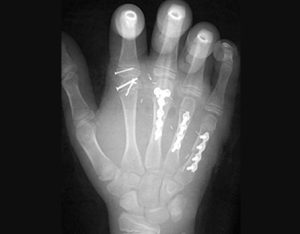

Parmak replantasyonu, bir kaza sonucu tamamen kopmuş veya kısmen ayrılmış parmakların, damarlar, sinirler ve tendonlar gibi yapıları mikrocerrahi yöntemlerle birleştirerek eski işlevine kavuşturulması işlemidir. Bursa parmak replantasyonu hizmetleri, acil ve planlı cerrahi prosedürlerle sunulmaktadır.

Replantasyon, bir kişinin vücudundan tamamen kesilmiş olan parmak, el veya kolun cerrahi olarak yeniden yerine takılması anlamına gelir (Amerikan El Cerrahisi Derneği, 2006).

Replantasyon ameliyatı amputasyonu takiben yapılan nihai yeniden yapılanma şeklidir. Benzer kompozit doku ve fonksiyonel iyileşme için en iyi şansı sağlar.

Sonuçta replantasyon ameliyatının amacı, hastaya yaralı bölgeyi mümkün olduğunca fazla kullanma olanağı sağlamaktır.